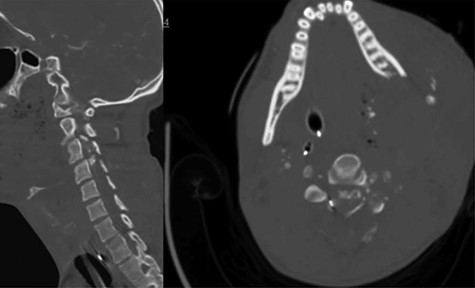

A 24-year-old African–American male presented with a gunshot wound through the left face and neck. On exam the patient was noted to be pulseless and apneic. After resuscitation, initiation of a mass transfusion protocol and return of spontaneous circulation, the patient was GCS 11 (E4V1TM6) and was noted to have no movement in any extremities. A computed tomographic (CT) cervical spine scan and CT angiography of the neck revealed a bullet trajectory through the left C2–3 facet with fractured c3 posterior elements and a bullet fragment at the C3 level, a left vertebral artery dissection, and left internal and external carotid artery transections (Fig. 1). The patient underwent an emergent tracheostomy, neck exploration, left ICA/ECA ligation and partial wound closure. This was followed by endovascular embolization of the left vertebral artery. The patient was noted to have serosanginous drainage from the neck wound consistent with a CSF leak. After an unsuccessful trail of conservative management, a lumbar drain was placed and confirmed with fluoroscopic guidance without CSF egress. A magnetic resonance imaging (MRI) scan of the cervical spine was obtained which demonstrated a pronounced CSF fistula and a complete obstruction of the CSF space at the C3–6 levels (Fig. 2).

MRI T2 weighted sequence sagittal (left) and axial (right) at the c3 level demonstrates severe spinal cord damage, canal obliteration from c3 to c6 and a large left sided csf fistula at the C3 level.

In the first case presented, surgical exploration for stabilization and CSF leak repair was offered, but the patient declined, the patient then underwent CSF diversion with a lumbar drain which was ultimately unsuccessful due to a physiologic myelographic block from c3 to c6 (Fig. 2). Ultimately the csf fistula was treated successfully after placement of an EVD. In the second case, there was a high index of suspicion of a csf block at the level of injury and a lumbar drain was not placed. The patient was successfully treated with CSF diversion through EVD for 7 days.